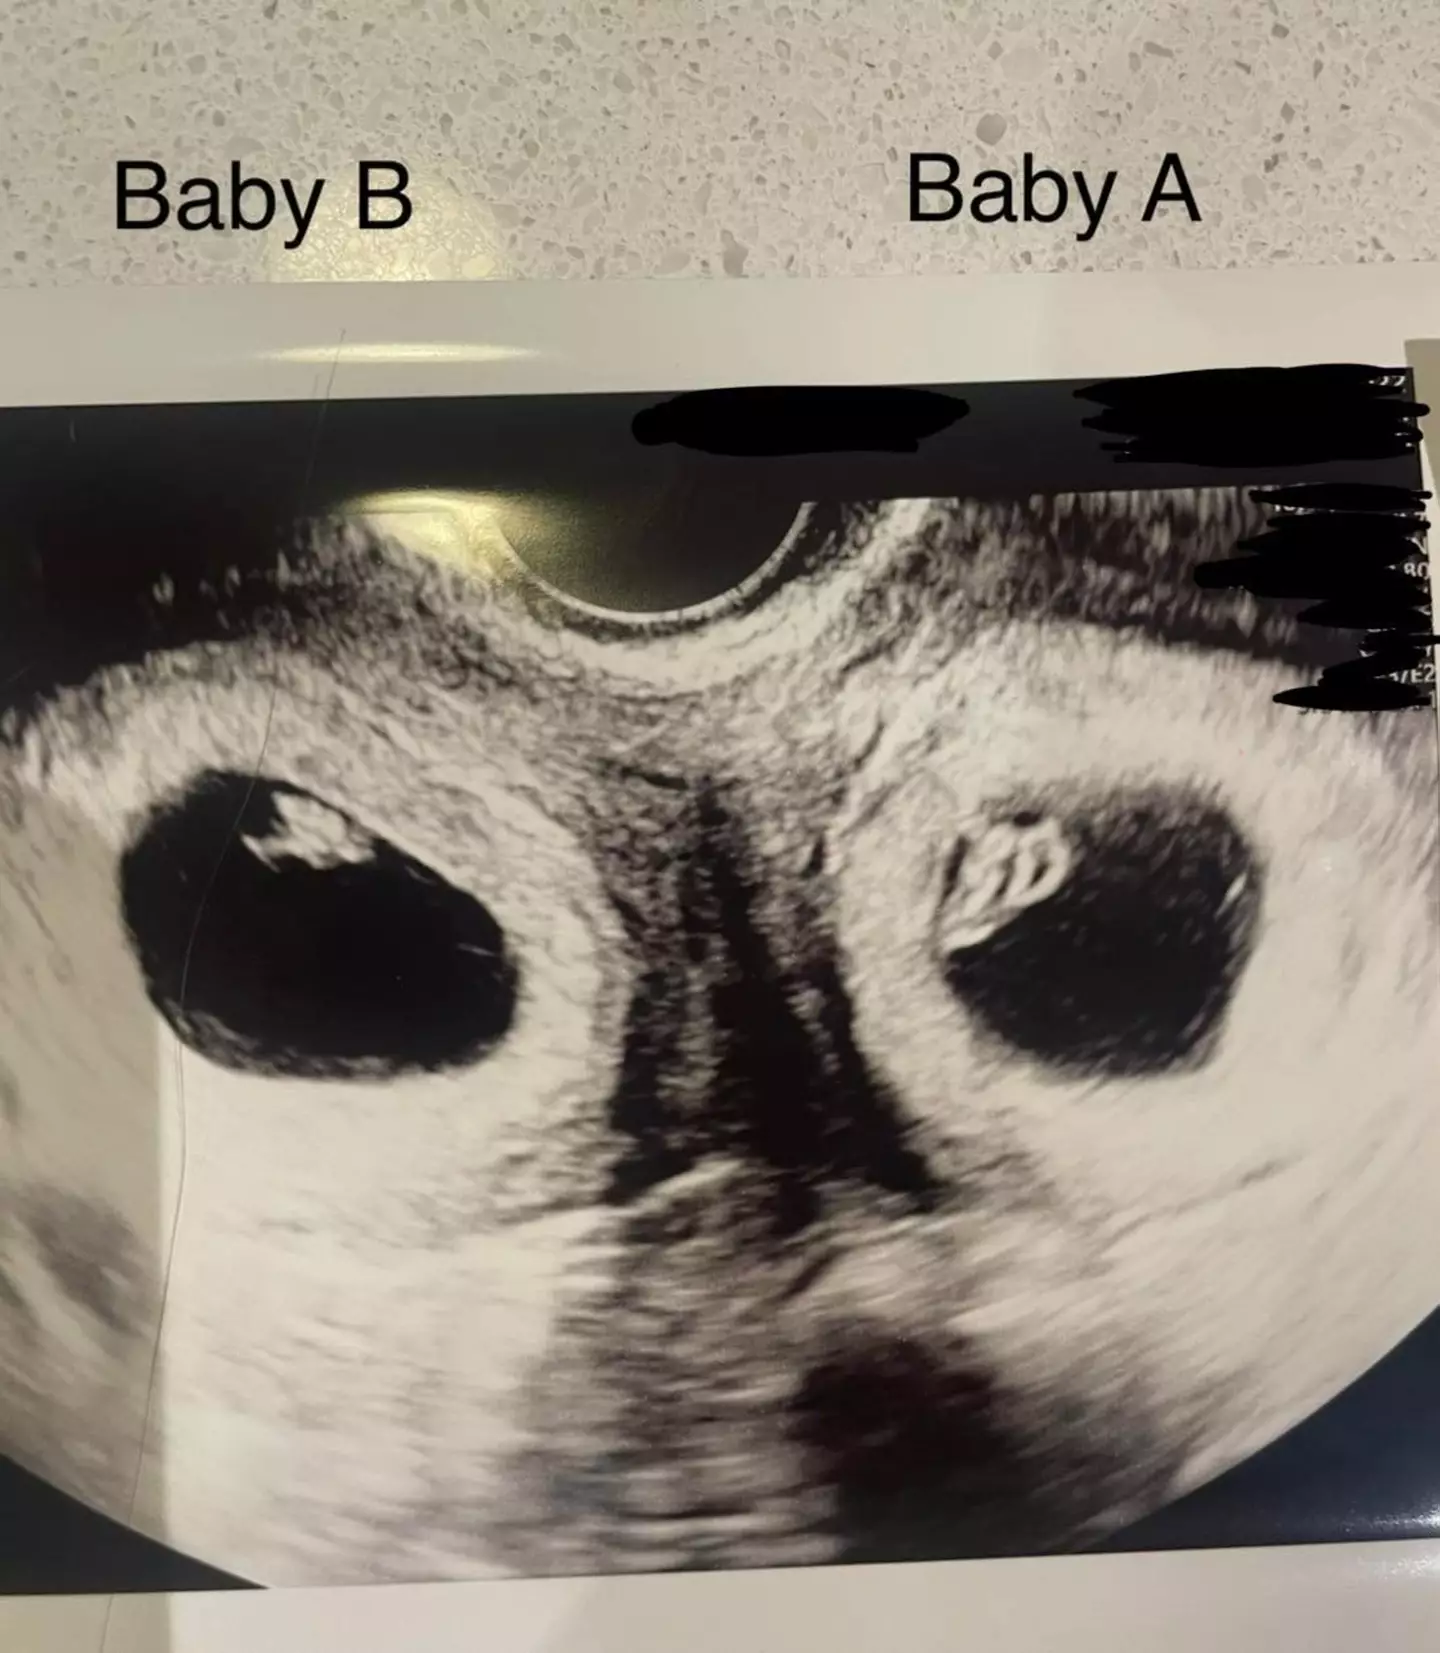

10 weeks later while going for a scan, the pair received the incredible news that Madeline was in fact carrying twins, one in each uterus.

The mum explained: "The pregnancy was classed as high-risk, and our doctor said a second baby could risk everything. We were terrified, but we both agreed that both of our twins were meant to be, so continued with both pregnancies. The pregnancy went fairly smoothly and I felt very safe because I was under constant monitoring."